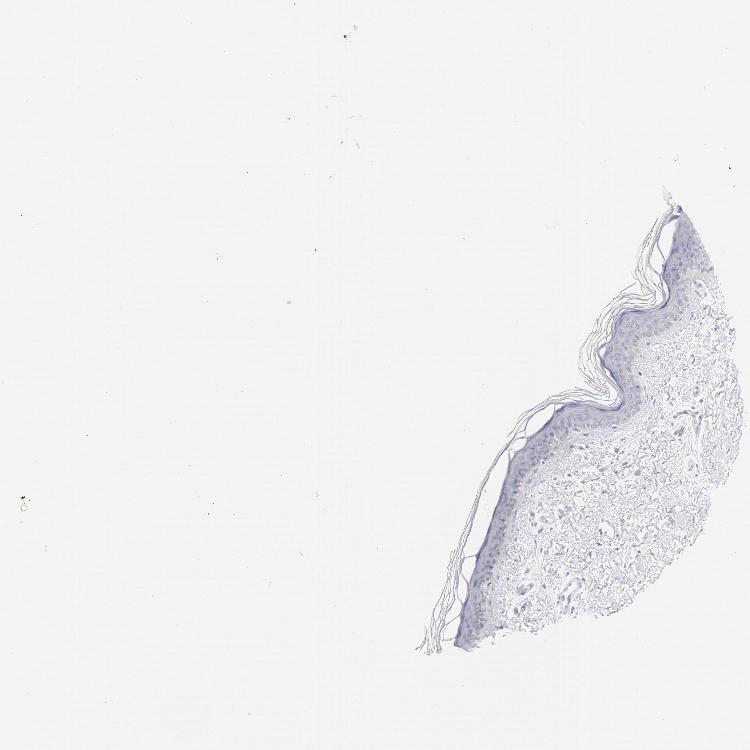

SKIN 1 - Antibody stainingi

Antibody staining in the annotated cell types in the current human tissue is reported as not detected, low, medium, or high, based on conventional immunohistochemistry profiling in selected tissues. This score is based on the combination of the staining intensity and fraction of stained cells.

Each image is clickable and will lead to virtual microscopy that enables deeper exploration of all samples and also displays staining intensity scores, fraction scores and subcellular localization as well as patient and tissue information for each sample.

Antibody HPA003316Antibody HPA003479

Langerhans Not detected-

Cells in basal layer -Not detected

Cells in corneal layer -Not detected

Cells in granular layer -Not detected

Cells in spinous layer -Not detected

Eccrine glands -Not detected

Endothelial cells -Not detected

Extracellular matrix -Not detected

Fibroblasts Not detected-

Fibrohistiocytic cells -Not detected

Keratinocytes Medium-

Langerhans cells -Not detected

Lymphocytes -Not detected

Melanocytes Not detectedNot detected

Vascular mural cells -Not detected